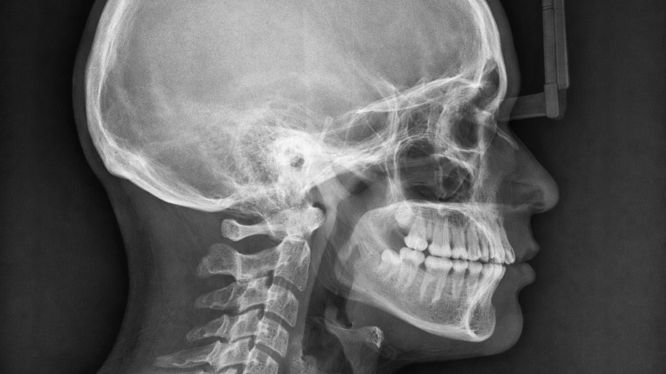

🔹 Radiografía lateral de cráneo

Es fundamental en ortodoncia.

Permite:

• Evaluar la relación entre maxilar y mandíbula

• Realizar trazado cefalométrico

• Predecir crecimiento facial

📌 Se solicita antes de tratamientos de ortodoncia, ortopedia o cirugía ortognática.

Radiografía lateral de cráneo